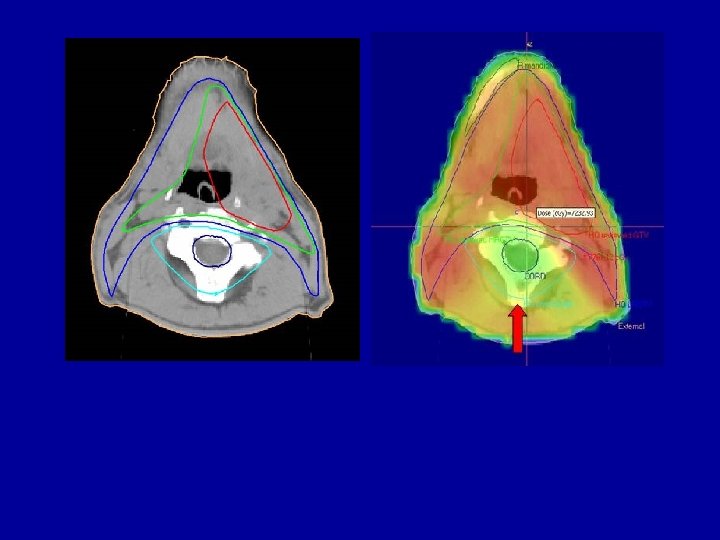

Radiotherapy - IMRT RT 3 D-CFRT Parotide glands IMRT Optimised beams to deliver the prescribed dose with maximum sparing S. Manolopoulos of the healthy tissue

Conventional Target Volumes around a cancer (red). OAR 1 OTV = remainder of body GTV Gross tumour volume GTV CTV PTV OAR 2 CTV Clinical target volume contains normal tissue PTV Planning target volume contains normal tissue OAR = Organs at Risk – within CTV, PTV and OTV

Normal tissue volumes which have to be treated